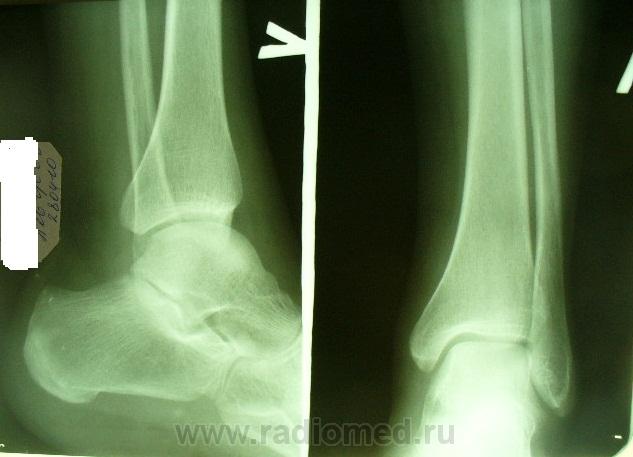

Ну вот, посоветовался с коллегами и самому легче стало. Я, не мудрствуя лукаво, в текучке написал норму. А нога-то болит... Пациент повторно пришел на прием. Вот снимки (желательно обработать).

Смущает некоторая порозность участка м/берцовой кости - жёлтые стрелки, и маловыраженная деформация м/берцовой кости - красные стрелки.

т.е. никто не угадал? перелом большой берцовой...

Там, где стрелка - не уверен. Обратил бы внимание на медиальную лодыжку.

Спасибо. Медиальная лодыжка не беспокоит, при пальпации локальная болезненность именно там где стрелка,но травму категорически отрицает. А на контроль скорее всего попадет не ко мне((((